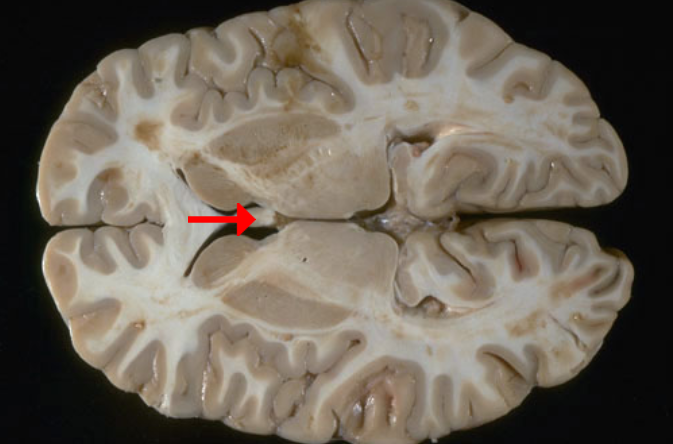

Label this brain structure

Middle temporal gyrus

Label this brain region of the temporal lobe

Inferior temporal gyrus

Label this brain structure

Optic chiasm